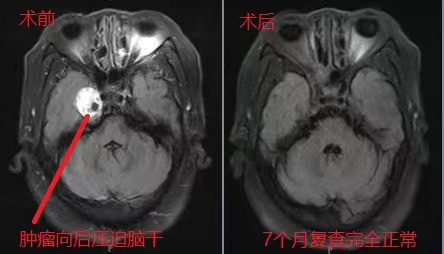

患者复查颅脑MR平扫+强化提示“右侧中颅窝肿瘤增大,向后侵犯后颅窝”。神经外五科团队术前讨论认为,该病例按常规方法可选择颞下入路开颅肿瘤切除术,但鉴于该病灶位于中颅底内侧,累及Meckel’s囊,以选择经鼻内镜下肿瘤切除术为更好。

经充分术前准备后,在科主任王喆带领下采取经鼻-筛-翼突入路侧颅底肿瘤切除术。术中磨除部分上颌窦,翼突和蝶窦骨质,依据解剖结构精确定位,直抵病灶,切开硬脑膜后,细致地分离并分块切除肿瘤,保护三叉神经,小心地分离肿瘤与颈内动脉地粘连,发现肿瘤起源于三叉神经半月节,与其粘连紧密。肿瘤切除后,空腔填塞患者自体脂肪,以鼻中隔粘膜瓣进行颅底重建,鼻腔填塞碘仿纱条。患者恢复顺利。